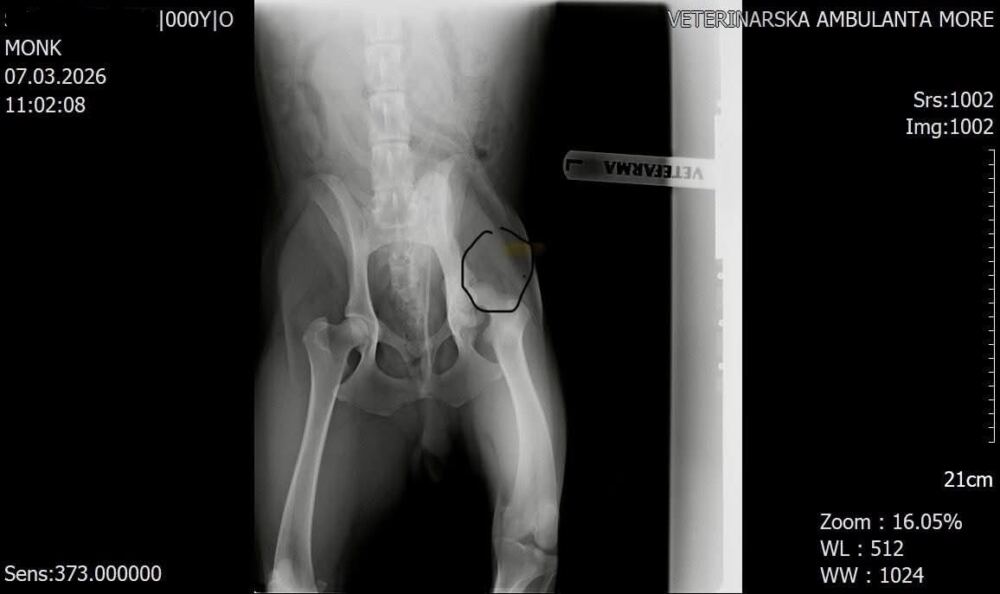

Teta čuvalica primijetila je da Monk ponekad čudno hoda. Odveden je na RTG pregled, a snimka je pokazala staru ozljedu – oštećen je lijevi stražnji kuk. Pretpostavlja se da je riječ o udarcu.

Monk mora na operaciju.

On je mlad pas, oko godinu i po dana star, i veterinar kaže da je operacija potrebna kako bi se mogao oporaviti i nastaviti normalno hodati – bez bolova i smetnji.